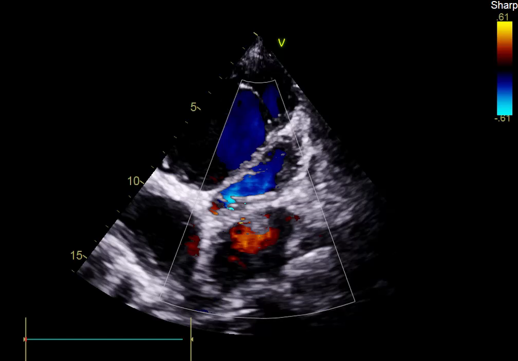

TEE, TEE and Floro showed both the leaflets to be stuck, almostno flow across the PV. The RV was higely dilated and there was severe RVdysfunction

Since TLT was not possible and surgeon refused for emergencyTranscatheter valve disruption was planned. The issues involve in the procedure were 1.Septal Puncture -due to pericardial patch in IAS, alteredanatomy due to Sx & ac dilatation of LA- Angle of puncture and Site ofpuncture. 2 Selection of wire3.Balloon- Size, make ( Compliant Vs NC), 4.Complication-like disc embolization, stuck disc leading to ac severe MA and strud fracture. The septa puncture was done as standard approach, a V18 wirewas parked in PV through a 7f Mullin sheath, Straight Turmo wire was was takenthrough a 6 JR to cross the valve and a 6 x 40 Armada balloon was dilatedacross the disc. Good acute result was obtained. The LA mean decreased from36-40 to 10-12mmHg. Post procedure the inotropic support, O2 demand decreasedover next 12 hr. However after 24 hr pt developed refractory RH failure and persistentanuria requiring SLED. And pt succumbed to the procedure 3 days after theprocedure.